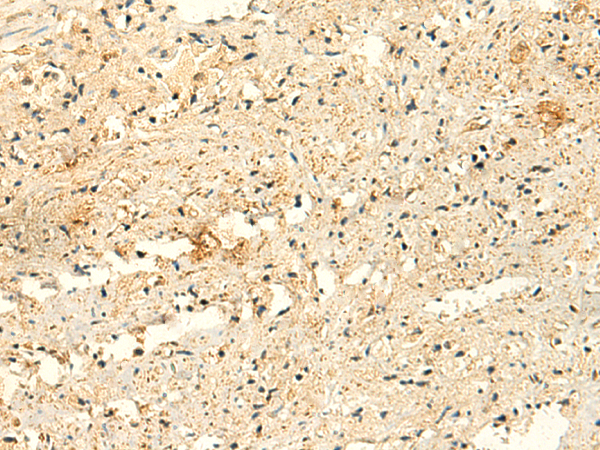

ELISA, IHC |

IHC positive control: |

Human tonsil and Human prostate cancer |

IHC Recommend dilution: |

50-300 |